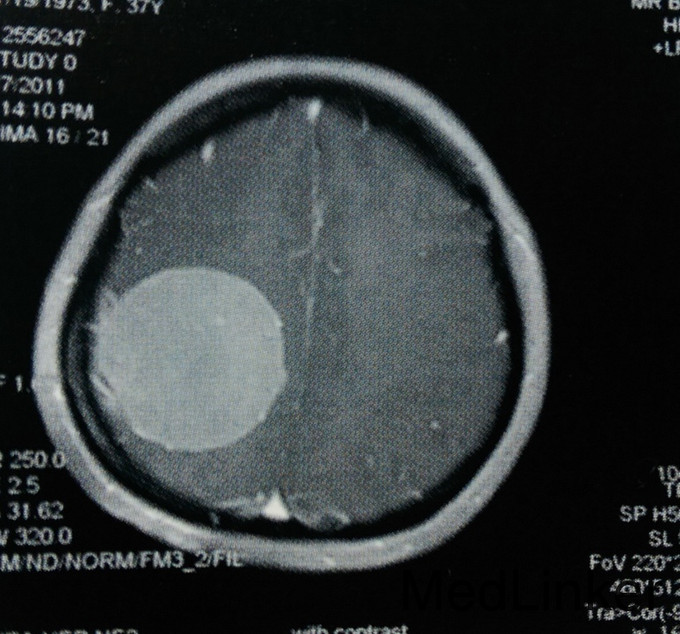

患者,女,37岁。主因左上肢麻木2年入院。 患者2年前无诱因出现左侧肢体麻木,无乏力、活动受限,未就诊。此后上述症状进行性加重,遂在当地医院以颈椎病对症治疗,未好转。行头颅MRI检查:右侧颞顶枕部见类圆形占位,大小约5.8cmх5.2cmх5.4cm,T1WI呈稍低信号,T2WI呈稍高信号,边缘尚清楚,压迫右侧脑室后角。Gd-DTPA增强后,明显强化,合并宽基底与脑膜相接,可见鼠尾征。门诊以“右顶叶巨大肿瘤”收入我科。无相关既往史、个人史及家族史。